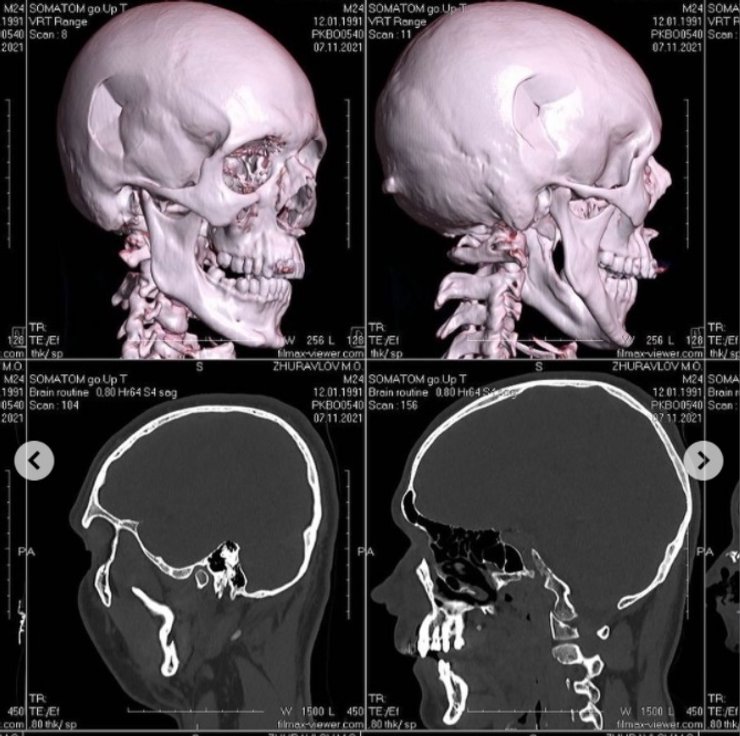

Инцидент произошел поздним вечером в подъезде дома, где живет Николай Журавлев. Парню теперь понадобится серьезная операция на черепе.

На композитора напали в подъезде девятиэтажки около 11 вечера 6 ноября. В итоге Журавлев получил химический ожог глаза, перелом носа, ушибы и другие травмы. Его госпитализировали в Александровскую больницу, где оказали первую помощь.

Медучреждение пострадавший покинул ночью со своей девушкой Дианой, которая сообщила полиции, что Журавлев сам обратится с заявлением к правоохранителям когда ему полегчает. Известно, что через месяц продюсеру нужно будет провести сложную операцию на черепе.

мрт